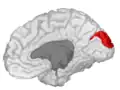

![]() Medial surface of left cerebral hemisphere. (Cuneus visible at left in red.) | |

The cuneus (from Latin 'wedge'; pl.: cunei) is a smaller lobe in the occipital lobe of the brain. The cuneus is bounded anteriorly by the parieto-occipital sulcus and inferiorly by the calcarine sulcus.

Position of cuneus(red) of left cerebral hemisphere.